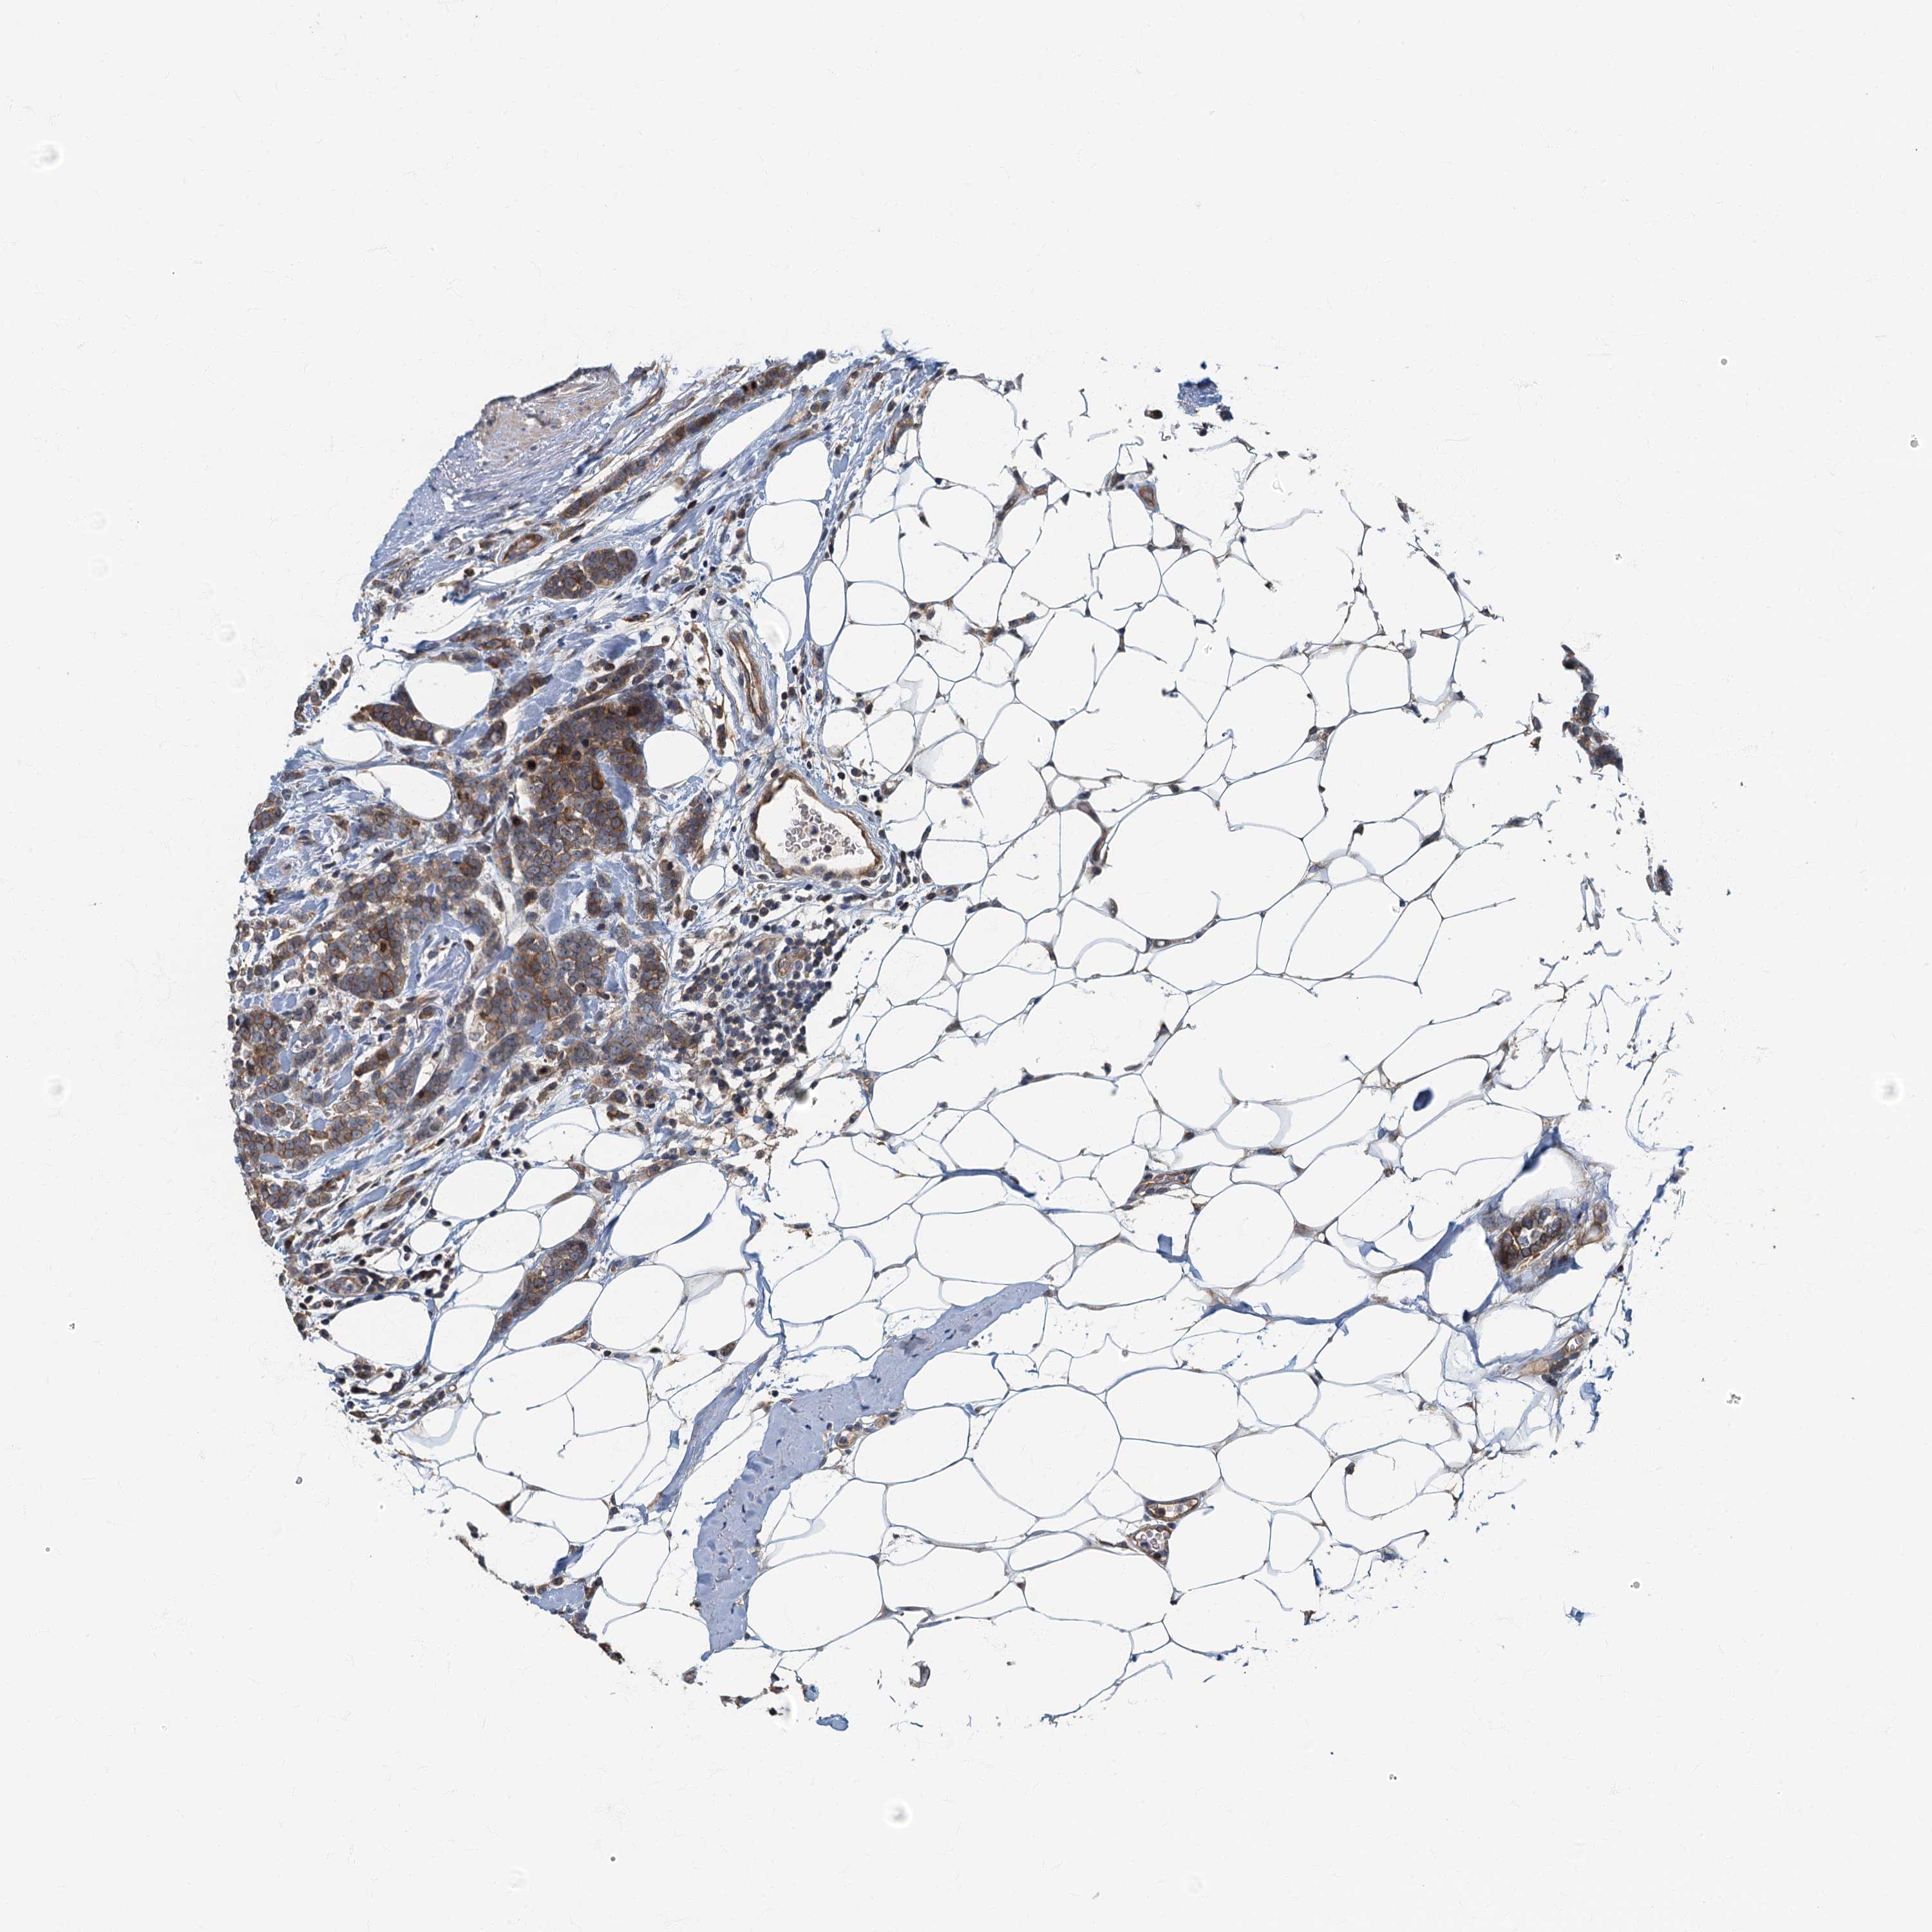

CANCER BREAST CANCER Show tissue menu

BRCA TCGA BRCA VALIDATION PROTEIN EXPRESSION